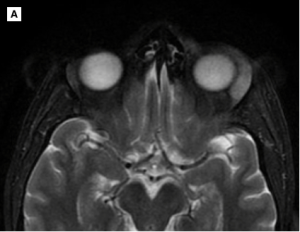

The choice of imaging study depends on the clinical context. CT scan and MRI can help localize and define the extent of the lesion in reference to 3-dimensional anatomy. However, when iodinated contrast media cannot be performed due to patient’s allergy to iodinated contrast, MRI is recommended for exact lesion characterization. ALHE can involve the orbit, lacrimal gland, eyelids, or less commonly conjunctiva. The most common site of involvement was superotemporal orbit. CT scan shows intense enhancement of the lesion following intravenous injection of contrast media. If the lacrimal gland is to be involved, inflammatory changes are usually noted. Lacrimal gland involvement is associated with preseptal thickening and infiltration of the superolateral compartment of the extraconal fat with enlargement of the extraocular muscles. The lesion is typically well circumscribed and located in the extraconal orbital compartment, abutting the lateral orbital wall and lateral zygoma. MRI can show the lacrimal gland exhibiting high T2/FLAIR and low T1 signal intensity with homogeneous enhancement on the post-contrast images. Evidence of globe infiltration was not reported in the literature.